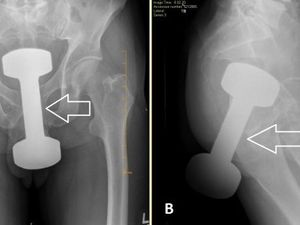

Seorang pria di Pennsylvania harus dirawat setelah dumbell 5 pon terjebak di rektumnya. Tim medis berhasil mengeluarkannya tanpa operasi.